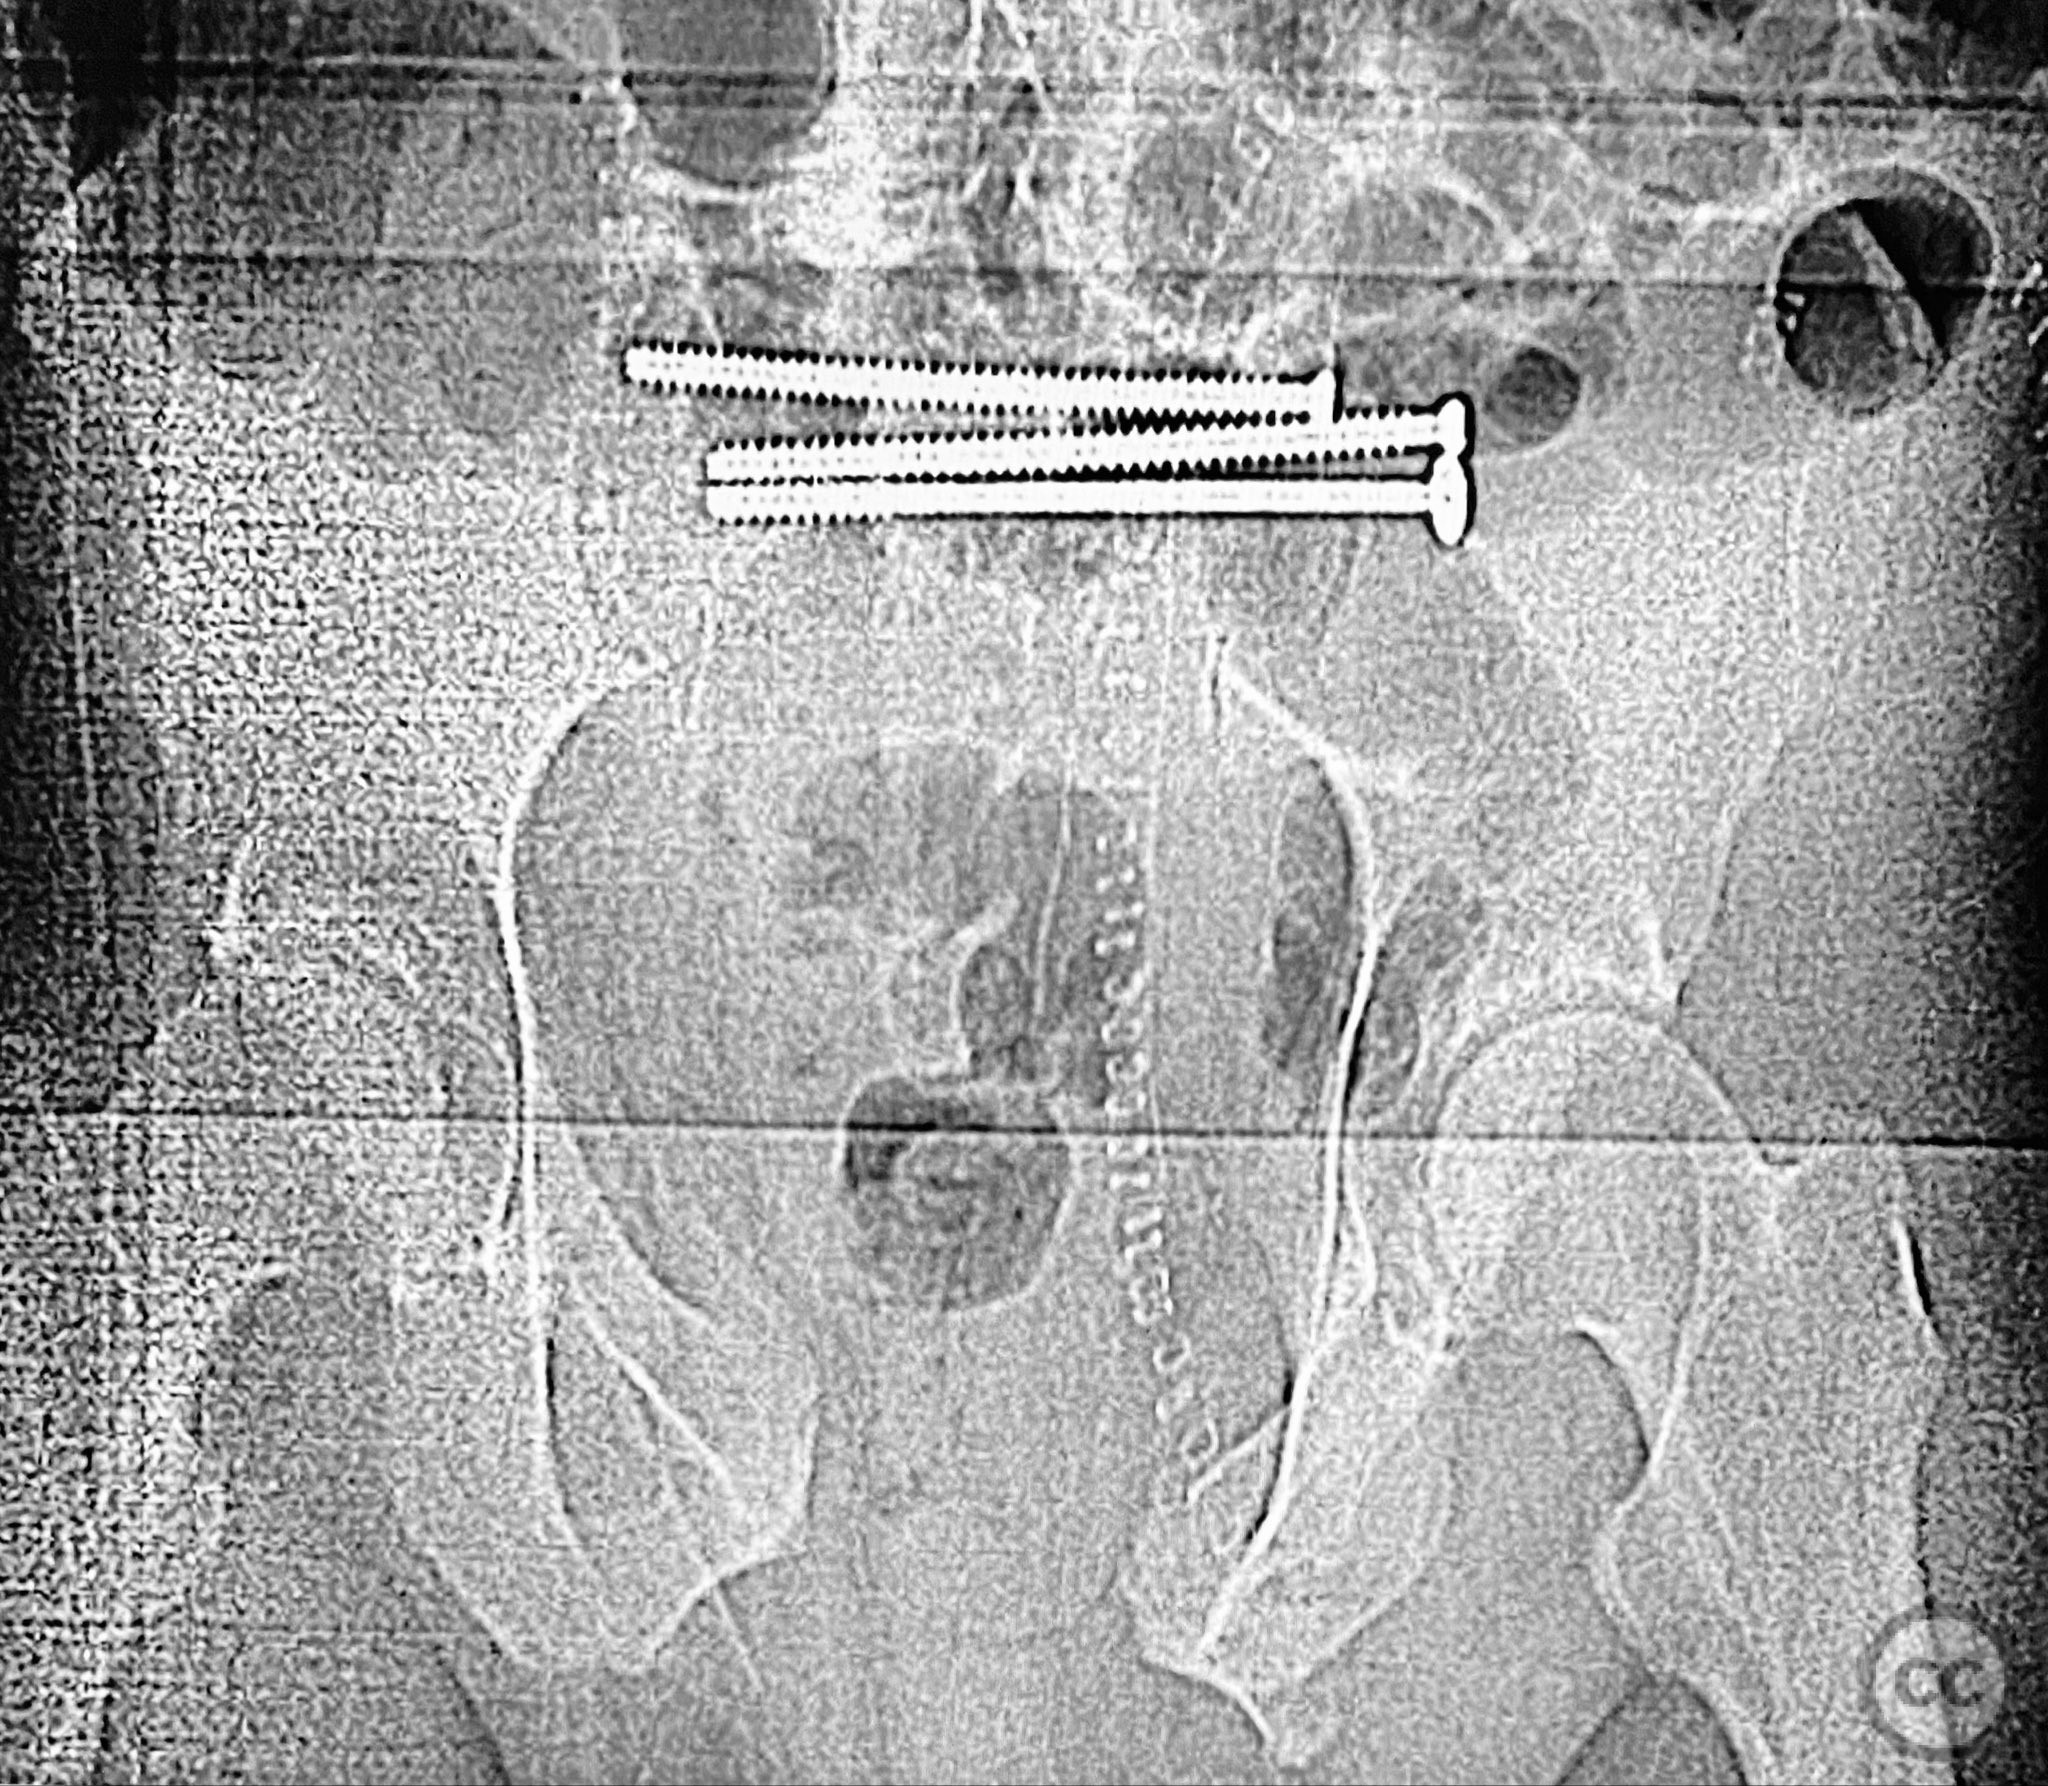

Planning remarks:  The preoperative plan included staged open reduction and internal fixation of the posterior pelvic ring via a dorsal approach in the prone position, utilizing direct visualization and reduction of the sacral fracture, followed by iliosacral and transiliac screw fixation. Definitive management of the anterior ring (symphysis pubis and ramus) was planned subsequently via an anterior approach in the supine position for reduction and stabilization.

The posterior reduction was facilitated by direct visualization of the dorsal sacral cortex, allowing precise assessment and clamping of the comminuted fragments prior to screw fixation. The iliosacral screws were placed without cannulated instrumentation longer than 130mm, reflecting historical implant limitations at the time of surgery. Postoperative CT confirmed satisfactory reduction and fixation of the posterior ring, though suboptimal positioning of iliosacral screws was noted (contained within the osseous fixation pathway but not optimized for maximal safety or precision). The anterior ring was subsequently addressed in a staged fashion, with anatomical reduction and stable fixation achieved via open technique. This case highlights technical challenges in achieving optimal screw trajectory and length, particularly with historical implant constraints, as well as the importance of staged management in complex pelvic ring disruptions.

Orthopaedic implants used:   7.3mm iliosacral screws (non-cannulated), posterior transiliac screw, anterior symphyseal plate, cortical screws for ramus fixation